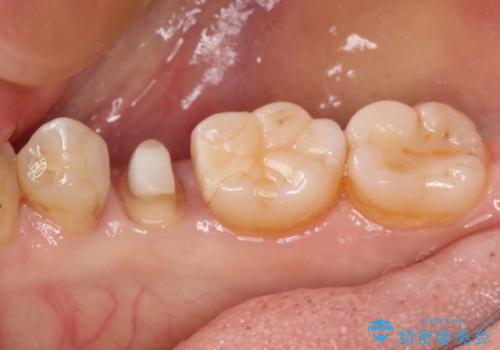

- 他院にて治療した詰め物が欠けてしまった事を主訴に来院された患者様です。

詰め物の範囲が大きく、部分的な詰め物では再び割れてしまうリスクが高いため、

オールセラミッククラウンにて補綴することとしました。

しみる症状はなくなり、見た目もきれいになり、とても満足されました。